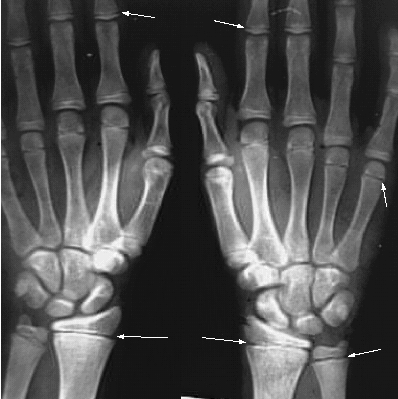

Upper Limbs:Growth Plates:

Arrows: Growth Plates of Radius, Ulna , Metacarpal Bones and Phalanges.